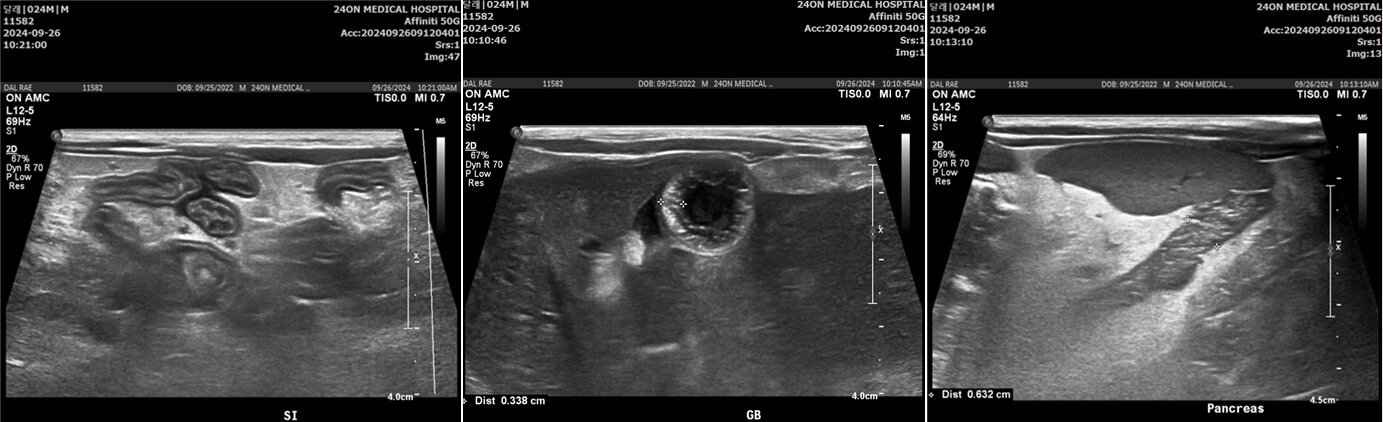

전문가들은 황달과 함께 원인 불명의 체중 감소, 소화 불편, 발바닥 가려움이 동시에 나타날 때 반드시 진료를 받을 것을 권고한다. 기본적인 혈액 검사로 빌리루빈 수치를 확인하고, 복부 초음파로 담도 폐색 여부를 파악하는 것만으로도 조기 이상 신호를 잡을 수 있다.